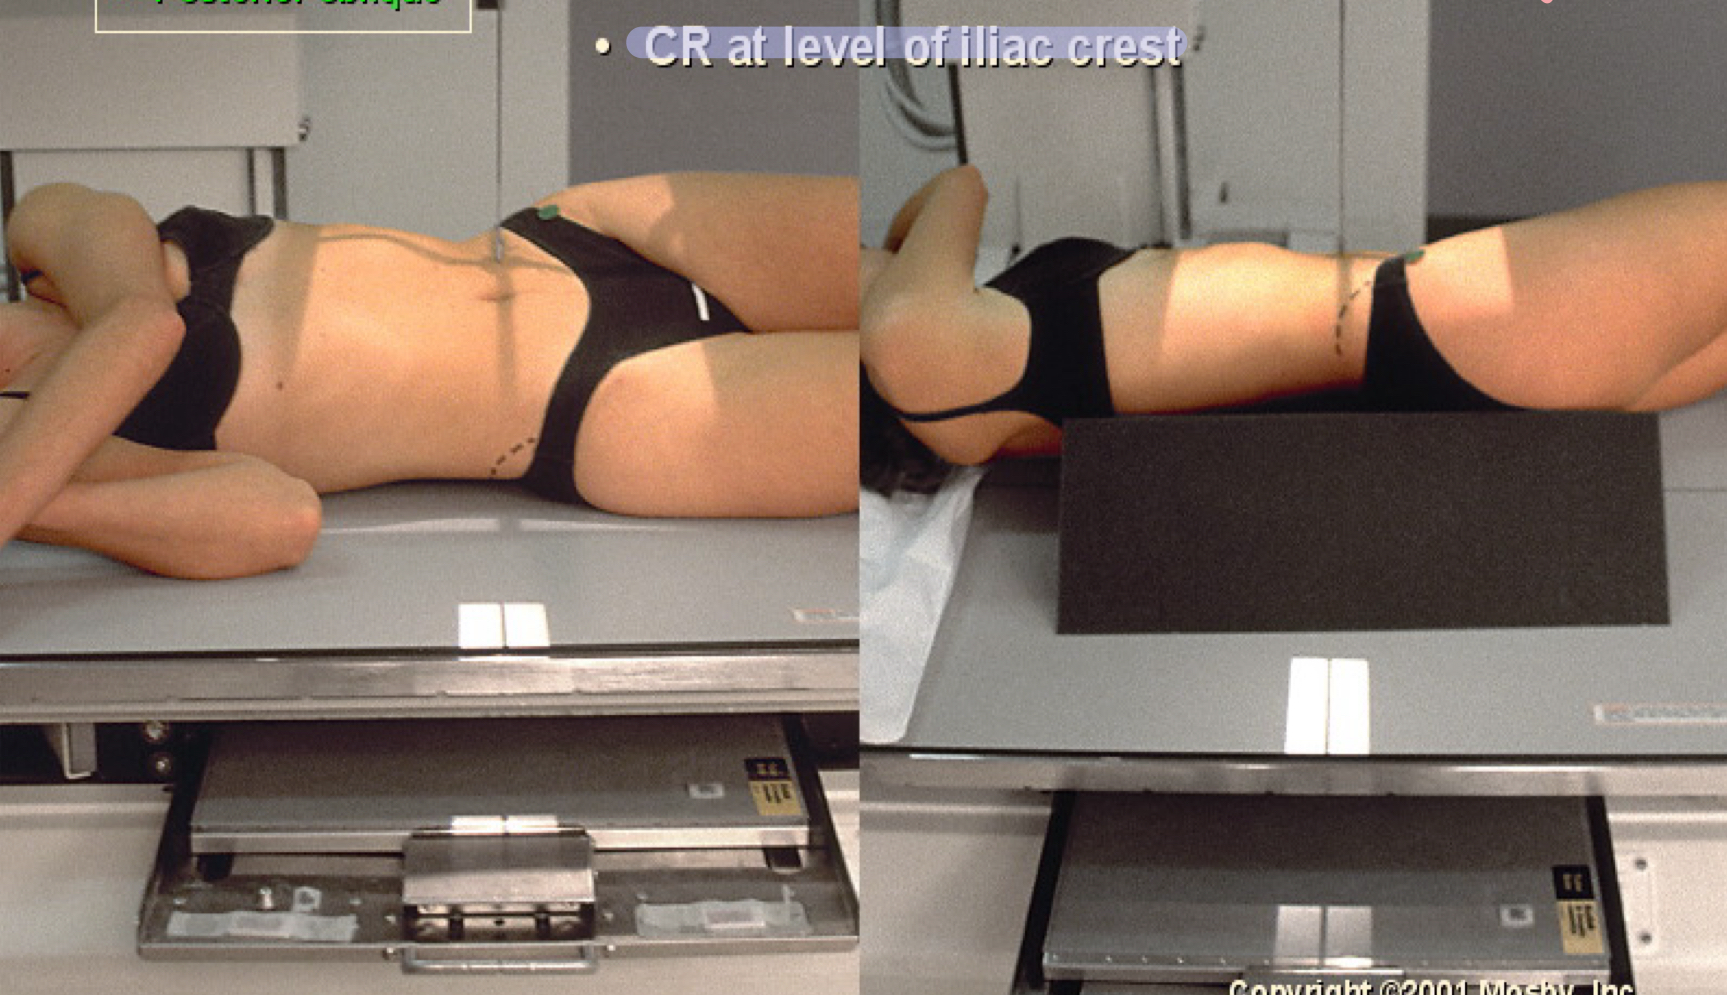

What position is this?

IVU posterior obliques